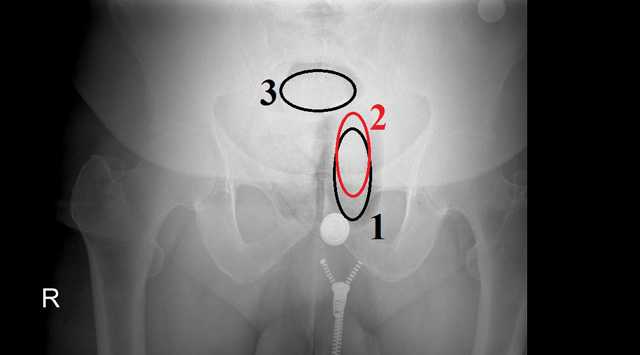

Bayburt’ta şüpheli şahsın anüs bölgesine gizlediği 71,65 gram uyuşturucu bulundu.

İl Emniyet Müdürlüğü görevlileri şüphelendikleri M.E.B. isimli şahsı sağlık kontrolü için götürdükleri hastanede, yapılan muayene esnasında anüs bölgesine gizlenmiş, 71,65  gram uyuşturucu ele geçirildi. Şüpheli şahıs yapılan işlemlerin ardından çıkarıldığı mahkemece tutuklanarak cezaevine gönderildi.

Uyuşturucu ve uyarıcı madde ticareti ve kullanımı ile ilgili yapılan operasyonlar kapsamında; durumundan şüphelenilen M.E.B. isimli şahsın alınan mahkeme kararı doğrultusunda Bayburt Devlet Hastanesi’nde röntgen ve tomografisi çektirilmiş, anüs bölgesinde 3 parça halinde olduğu görülen toplam ağırlığı 71,65 gram metamfetamin maddesi ele geçirildi. M.E.B. isimli şahıs sevk edildiği adli makamlarca uyuşturucu veya uyarıcı madde imal ve ticareti suçundan tutuklanarak cezaevine teslim edildi.